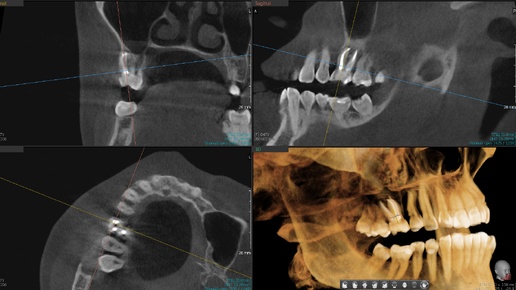

Кость восстановилась полностью за два года после перелечивания каналов - пропущенный МВ-2, периодонтит и два контрольных КТ

Аномалия. Почти все терапевтические статьи на канале начинаются со слов: "Этот зуб в других клиниках рекомендовали удалить". Но из песни слов не выкинешь. 2024 год (сейчас 2026). Пациентка обошла несколько стоматологий, прежде чем попасть в Parodent. И каждый врач в каждой из них выносил один вердикт - зуб не спасти. А потом наш хирург посмотрел КТ и сказал: "Удалять не надо. Сходите к Обмайкину на перелечивание". А у нас даже микроскопа в те времена не было! И вот, прошло почти два года. Сейчас покажу, что за зуб такой и что с ним стало...